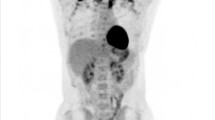

There were 62 patients (54 women, eight men) who had active cancer on PET/CT and 80 patients (67 women, 13 men) without active cancer. None of the patients in the active and non-active cancer groups had cancer cachexia. There was no significant difference in the time interval between the last form of treatment and PET/CT between the groups (active vs. non-active cancer: 11.5 ± 19.5 months vs. 19.6 ± 20.7 months, p = 0.2). Outside temperature at time of PET/CT was similar between the groups with and without active cancer. Groups were similar in age, sex, fasting glucose, and BMI, abdominal and muscle CSA. Patients who had active cancer on PET/CT had higher BAT volume compared to patients without active cancer (Figs. 1 and 2).

A 56-year-old woman with non-small-cell lung cancer (BMI: 25 kg/m2). Axial PET image (a) demonstrates increased FDG uptake in the supraclavicular areas, which corresponds to fat attenuation on the CT (b) and fused PET/CT (c) (white arrows). Coronal PET (d) and fused PET/CT images (e) demonstrate the extent of brown adipose tissue (BAT), which was 28 ml (white arrows). Note increased FDG uptake of active lung cancer (gray arrows). Axial CT (f) demonstrates the non-small-cell lung cancer (arrow)